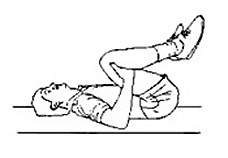

일하던 중이나 잠자리에서 일어나다가, 아니면 이삿짐을 나르다가 허리가 삐끗한 경우 허리에 통증이 올 수 있다. 이 때는 당황하지 말고 바닥에 누운 후 무릎을 구부린다. 양손으로 깍지를 낀 후 구부린 무릎을 가슴 쪽으로 당기고 턱도 가슴 쪽으로 당겨 몸을 공처럼 굴린다. 특히 넘어지거나 무거운 물건을 나르다가 허리를 삐끗하면 몸은 이도 저도 못할 정도로 통증이 심한 데, 이렇게 급성 요추 염좌 같이 통증이 심할 때는 바닥에 누워 무릎높이 만큼의 의자나 이불을 괴어놓고 그 위에 다리를 얹는다. 그 다음 책이나 수건을 말아서 엉덩이에 받쳐주고 무릎을 바라볼 수 있도록 베개를 약간 높은 것을 선택한다. 이러한 자세를 하고 있으면 허리가 한결 부드러워진다. 또 환자의 양쪽무릎을 가슴까지 밀어주는 운동을 10여 차례 반복하면 통증이 감소된다.

그림 2. 복부 근육 강화 운동. 만성요통으로 혈액순환이 잘 되지 않을 때 더운찜질을 하면 일시적으로 좋아질 수 있지만 너무 많이 할 경우 근육이완을 불러 더욱 악화될 수 있다. 허리와 골반주위의 인대들이 이완되면 자세가 나쁠 때 척추가 비뚤어지기 쉽고 그 사이의 디스크가 밀려나와 부어 오를 수 있다. 허리에 통증이 있으면서 화끈거리며 열이 나면 얼음찜질을 하는 것이 효과적이다. 물에 적셔 꼭 짠 수건에 얼음 덩어리를 몇 개 넣고 굴리듯이 마사지하면 감각이 마비된 듯 하다가 통증이 사라진다. 특히 허리를 삔지 3일 이내, 급성 요추 염좌일 경우 근육과 인대가 충격을 받아 열이 나기 때문에 즉시 얼음찜질을 해서 열을 식혀주고 이완된 근육과 인대도 원상태로 수축시켜 줘야 한다. 찬찜질은 여러 가지 방법이 있으나 일반적으로 가장 효과가 좋은 것은 얼음덩어리를 직접 사용하는 방법이다. 나무 젓가락이나 나무 막대기에 얼음을 붙여 사용한다. 이것은 쉽게 만들 수 있는데, 냉장고 속에 종이컵에 물을 채워 넣고 그 속에 손잡이가 될만한 나무 조각을 넣어 같이 얼면 종이컵을 얼음에서 떼어버리고 얼음덩이를 손잡이를 이용하여 허리에 문지른다. 얼음 맛사지는 허리가 아픈 부위에 10분 내지 12분간 시행한다.

그림 4. 복부 근육 강화 운동. 더운 찜질도 요통에 효과가 있는데, 열이 피부를 통하여 허리로 들어가 진통역할을 하기 때문이다. 그러나 더운찜질은 찬찜질과 반대로 혈관을 확장시키기 때문에 허리를 더욱 붓게 만들므로 허리를 다쳐서 근육 등이 부은 부분은 더운찜질은 하지 않는 것이 좋다. 허리가 아픈 사람마다 자신이 가장 편안해 하는 어떤 자세가 있는데 허리가 아플 때 추천할 수 있는 자세는 의자 위나 침대 위에 발을 얹어놓고 방바닥에 등을 대고 눕는 자세이다. 이때 두개의 베개를 사용하면 좋은데, 하나는 머리 밑에, 다른 하나는 엉덩이 밑에 받치도록 한다. 그리고 윗몸을 의자에 가까이하여 무릎이 가슴쪽으로 구부러지도록 한다.